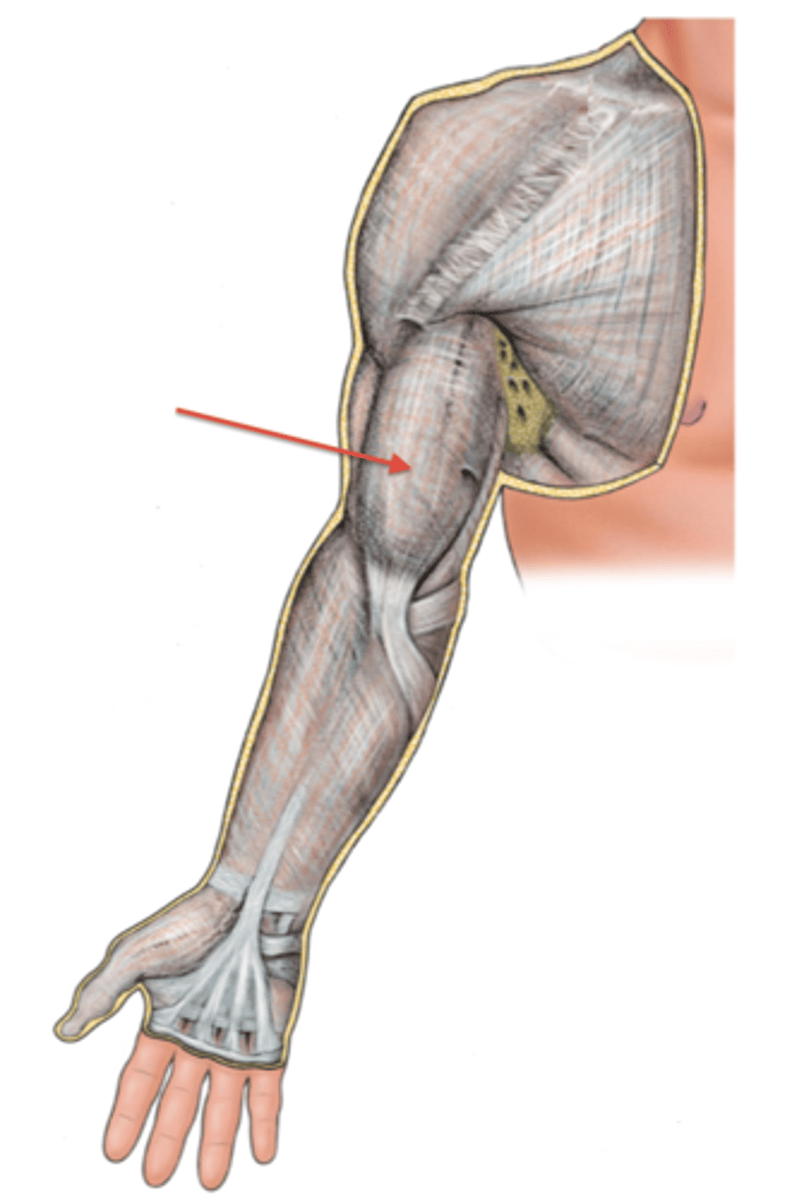

(Upper limb fascia) Fascia of arm region

Brachial fascia

(Fascia of arm region:) Brachial fascia

sheath of deep fascia that encloses the arm like a sleeve deep to skin and superficial fascia. It is continuous superiorly with the deltoid, pectoral, axillary, and infraspinous fascias, and inferiorly with the antebrachial fascia (at the level of the elbow)

- Contains Medial & Lateral intermuscular septa

(Brachial Fascia:) Medial & Lateral intermuscular septa

extensions of brachial fascia that attach to the bone, forming fascial compartments that limit spread of infection and hemorrhage in the arm

-Anterior (flexor) fascial compartment

-Posterior (extensor) fascial compartment

(Upper Limb Fascia:) Fascia of forearm region

Antebrachial fascia

(Fascia of forearm region:) Antebrachial fascia

sheath of deep fascia that encloses the forearm like a sleeve deep to skin and superficial fascia. It is continuous superiorly with the brachial fascia, and it thickens inferiorly to form bands over the distal portion of the radius and ulna

-Contains: Medial & Lateral intermuscular septa and Transverse bands

(Antebrachial fascia:) Medial & Lateral intermuscular septa

extensions of brachial fascia that attach to the bone, forming fascial compartments that limit spread of infection and hemorrhage in the forearm

-Contains Anterior (flexor) fascial compartment and Posterior (extensor) fascial compartment

(Antebrachial fascia:) Transverse bands

-Extensor retinaculum

-Flexor retinaculum (transverse carpal ligament)

-Palmar carpal ligament

(Antebrachial fascia's Transverse bands:) Extensor retinaculum

in the posterior region, retains extensor tendons in place

(Antebrachial fascia's Transverse bands:) Flexor retinaculum (transverse carpal ligament)

forms the roof of the carpal tunnel, which contains flexor tendons and the median nerve

(Antebrachial fascia's Transverse bands:) Palmar carpal ligament:

in the anterior region superficial to the flexor retinaculum, and continuous with the extensor retinaculum in the posterior region